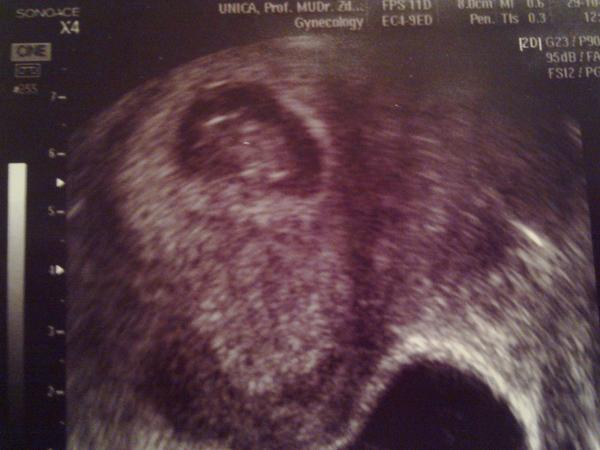

@pupidu já to měla rychlé, pan dr si pochvaloval, jak bylo vše krásně vidět, i když pak napsal že né, protože jsem kulička 😀

@zelvik nooo, on tam seděl jak na nočníku, nedalo se to přehlédnout 😀